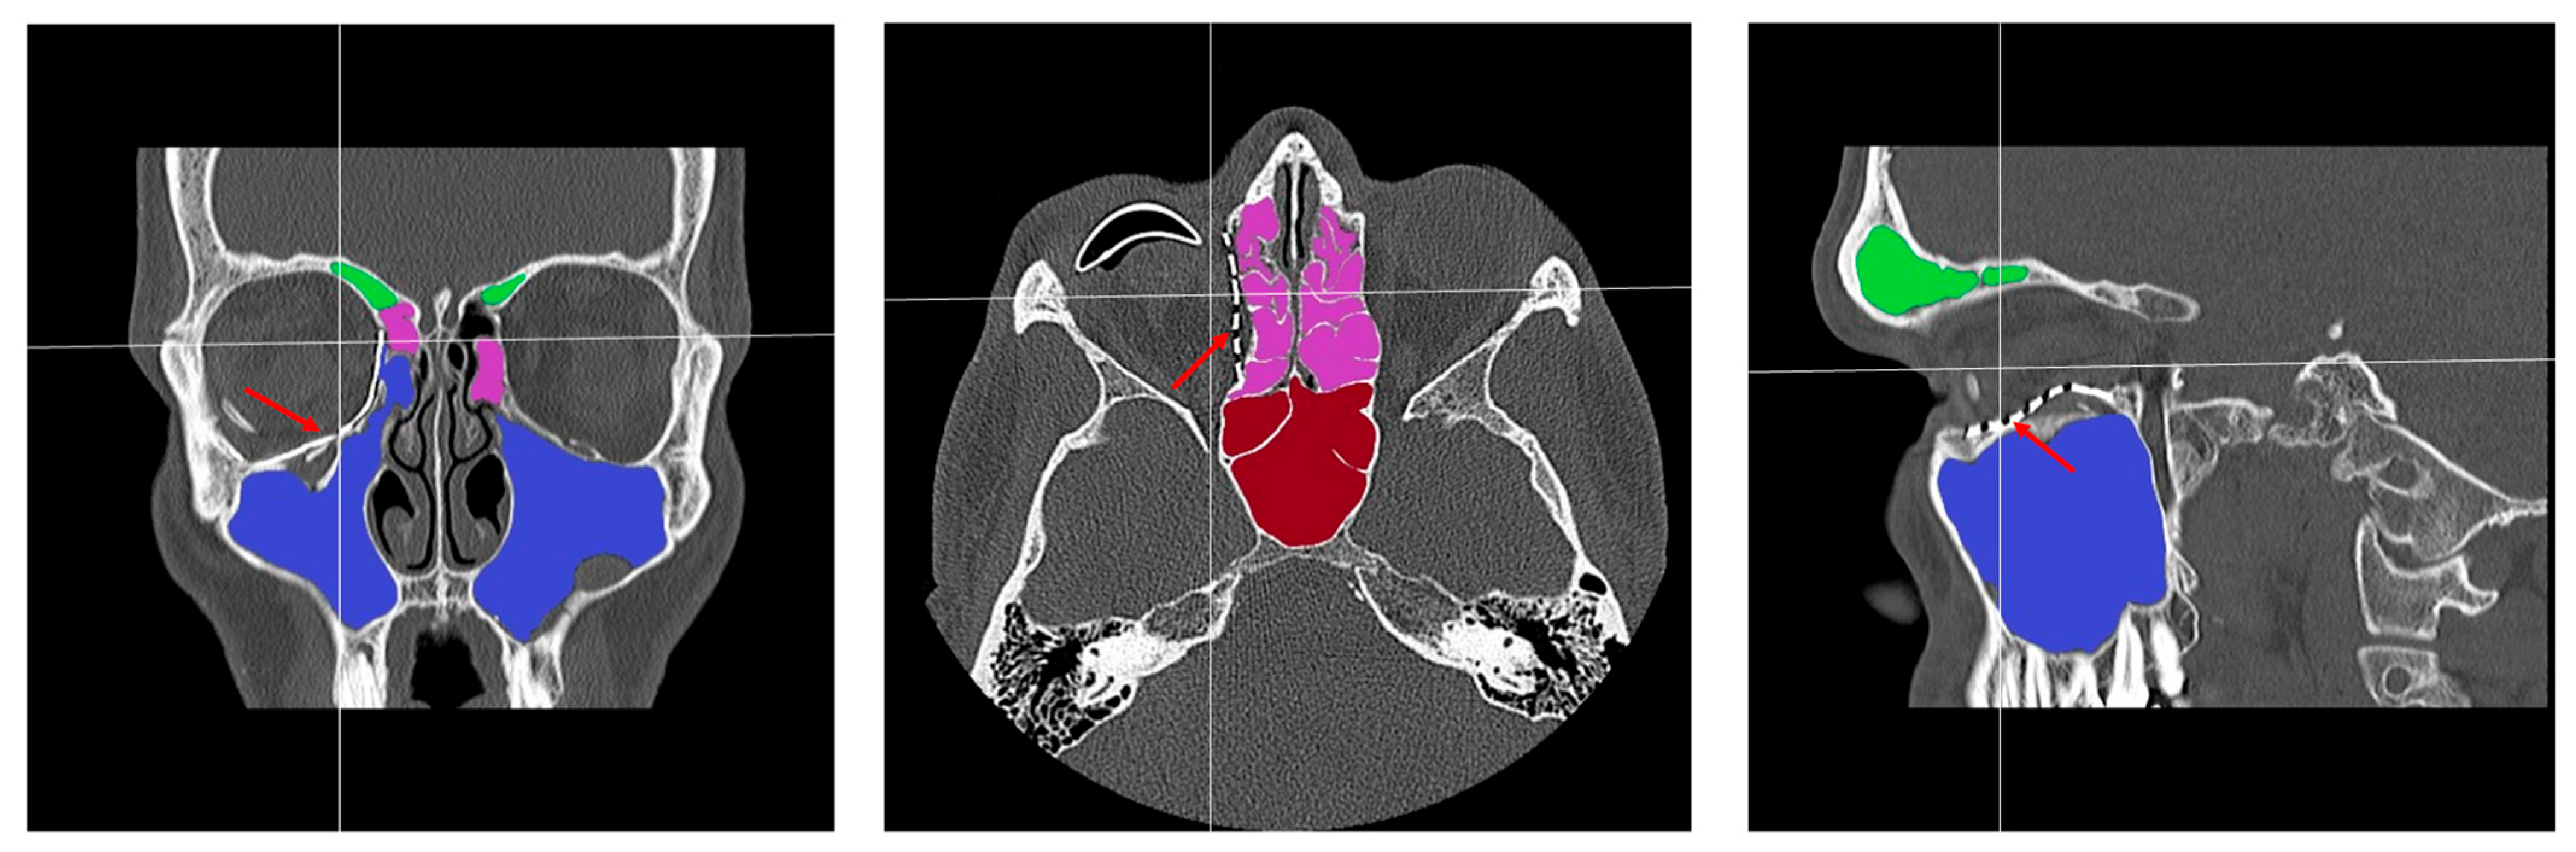

- Patent ostium of the maxillary sinus (coronal plane)

- Non-inflammatory PNSs (three planes)

- Exposure of the osteosynthesis screws (axial and sagittal planes)

- Exposure of the PSI to the maxillary sinus (coronal and sagittal planes)

- Remodeling of the fractured orbital walls and bone apposition at the PSI indicating osseointegration (three planes)

- Patent outflow tract of the maxillary sinus (n = 14) and physiologically ventilated PNSs (maxillary sinus, ethmoid cells, n = 13)

- Exposure of the fixation screws (infraorbital recess of the maxillary sinus) and limited exposure of the PSI (transition zone, ethmoid cells) without signs of mucosal swelling in these regions (n = 6 each)

- (Basal) mucosal swelling in the maxillary sinus indicative of chronic maxillary sinusitis, irrespective of the complexity of the primary injury (n = 4)

- Bone apposition at the PSI as a sign of osseointegration (n = 16)

- Remodeling of the dislocated bone fragments of the orbital walls (n = 16), including in the area of the infraorbital canal.